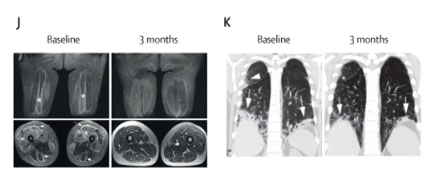

圖9:患者肌炎的病變完全消退且呼吸道癥狀有所改善

2023年2月,Georg Schett 團隊等人在《柳葉刀》發(fā)表臨床研究論文:CD19-targeted CAR-T cells in refractory antisynthetase syndrome[4],使用CAR-T細胞療法成功治療了一種新的自身免疫疾病——特發(fā)性炎性肌病。

這名患者患有自身免疫疾病特發(fā)性炎性肌病的亞型——抗合成酶抗體綜合征(圖6)。這是一種嚴重的自身免疫性炎癥性肌肉疾病,該疾病是由于體內(nèi)參與氨基酸合成的氨酰-tRNA合成酶被免疫系統(tǒng)錯誤攻擊所導致的,從而影響各種細胞的功能。

這是世界首個使用CAR-T細胞療法成功治療的抗合成酶抗體綜合征患者,也是繼系統(tǒng)性紅斑狼瘡后,第二種被CAR-T成功治療的自身免疫疾病。